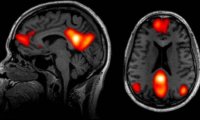

Неожиданная польза скуки: как мозг использует паузы для восстановления

Нейронаука раскрывает удивительную пользу скуки: она перезагружает мозг, усиливает креативность и снижает тревожность. Узнайте, почему периоды ничегонеделания стали дефицитным ресурсом в нашем...